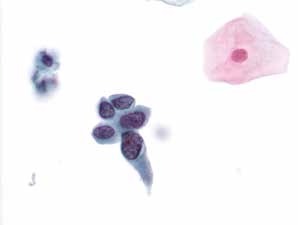

图4-9 非典型鳞状细胞,不除外高度鳞状上皮内病变(ASC-H)(高倍、液基、巴氏染色)

背景干净,细胞核明显增大,染色深,胞质少,核质比明显增高,因单个出现,数量少,可诊断为ASC-H或HSIL。